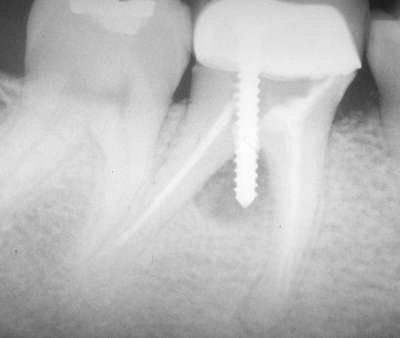

Question 11: Which materials cannot be seen in the print of the X ray?

Question 12: What option cannot be selected for the following X ray?

Question 13: What option cannot be selected for the following X ray?

Question 14: Which surface shows overhang restoration?

Question 15: Which surface shows overhang in the restoration?

Question 16: Which surface shows overhang?

Question 17: Which surface shows overhang?

Question 18: Which surface shows overhang?

Question 19: Which option can be chosen for the tooth # 3.6?

Question 20: which tooth shows defective resotration?